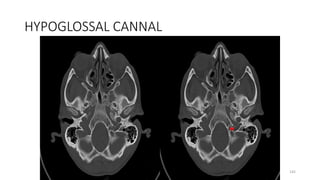

Hypoglossal canal

Hyoglossal canal

HYPOGLOSSAL CANNAL